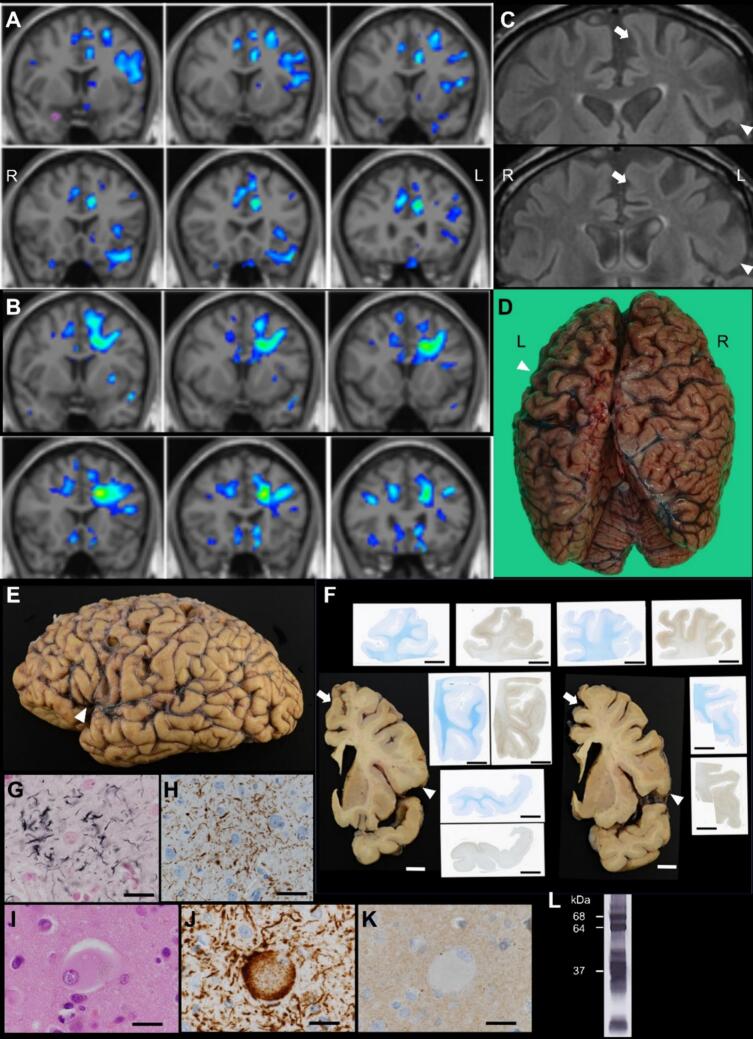

Although the patient’s voluntary speech continued to decline, grammatical or articulation impairments were not noted. Follow-up MRI, including voxel-based morphometric analysis, suggested only a mild reduction in gray matter volume in the left frontal lobe (Fig. 1A). However, reduced white matter volume was observed in the left frontal lobe, including the area between the left SMA/preSMA and frontal operculum (Fig. 1B). Mild high-intensity signals were also observed on fluid-attenuated inversion recovery (FLAIR) images in the left frontal white matter (Fig. 1C). The patient became completely mute, and using utensils with his right hand became difficult two years after disease onset. Three years after the disease onset, the patient exhibited akinetic mutism and died of aspiration pneumonia. Autopsy was performed after permission from the patient’s family.

The brain weighed 1,020 g. During autopsy, pronounced left-dominant frontal lobe atrophy and left parietal lobe atrophy were observed at the convexity (Fig. 1D) and in the lower precentral gyrus, frontal operculum, and anterior superior temporal gyrus (Fig. 1E). Sagittal sections showed frontal volume reduction in both gray and white matter, including the white matter between the medial superior frontal gyrus and frontal operculum, in addition to white matter discoloration. Semimacroscopic images revealed intense phosphorylated tau staining in the gyri (Fig. 1F). Microscopic examination revealed astrocytic plaques and ballooned neurons, positive for phosphorylated tau and 4-repeat tau, present in the left medial superior frontal gyrus, frontal operculum, and subcortical white matter, which was consistent with the observed macroscopic changes (Fig. 1G-K). Western blotting analysis of sarkosyl-insoluble tau revealed bands of approximately 37 kDa (Fig. 1L). Based on these findings, the patient was pathologically diagnosed with CBD.